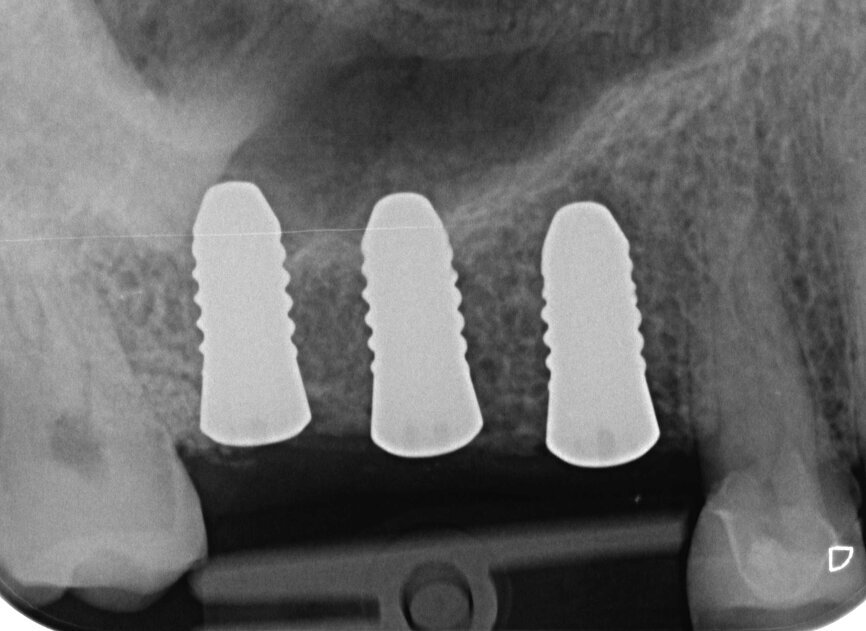

Fig. 17 : Radiographie de contrôle postopératoire.

Mélangés avec du sang prélevé au niveau du site chirurgical du patient, les granules poreux de phosphate tricalcique bêta d’origine synthétique sont faciles à appliquer. Au bout de six à neuf mois, le matériau se régénère en os cortical stable. Après le recouvrement des implants par une coiffe de protection en polyéther éther cétone (PEEK), la plaie a été fermée sans tension au moyen de deux sutures matelassées et plusieurs sutures simples discontinues (Fig. 16). Ensuite, une radiographie a été prise pour un contrôle (Fig. 17). 8 Le patient a quitté le cabinet dentaire avec de nouvelles instructions concernant la conduite à tenir après l’intervention, insistant sur les soins et l’absence de toute pression.